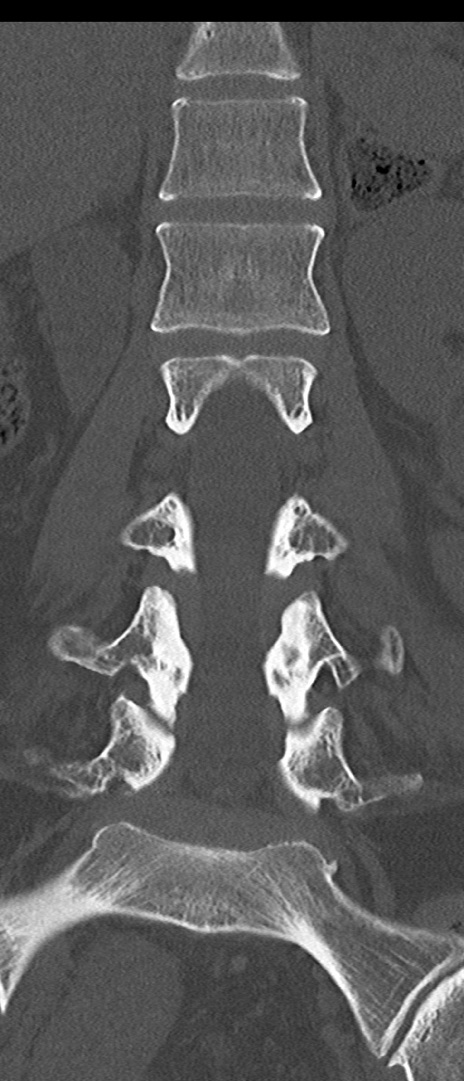

【整形】TIPS症例4 腰椎CT(冠状断像)

腰椎CT